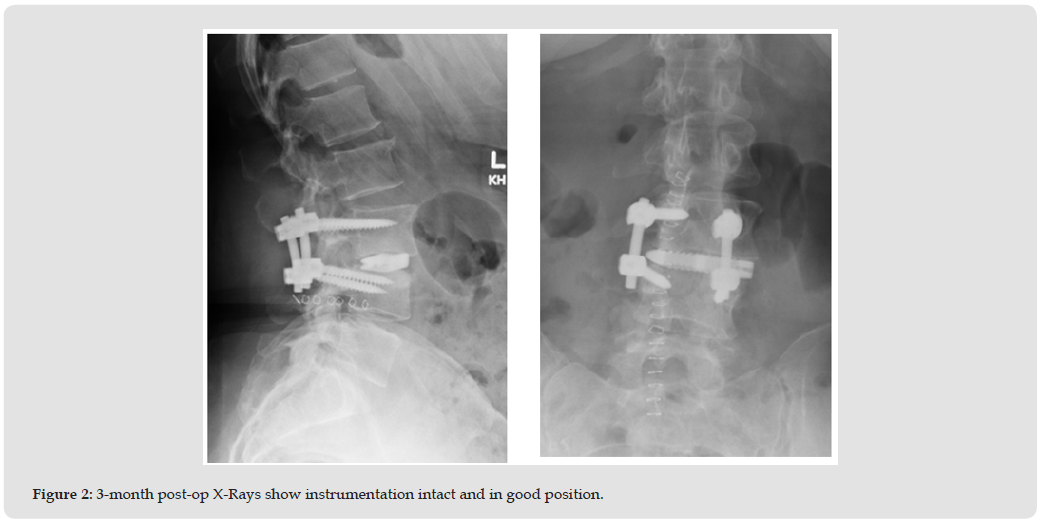

The patient was a 54-year-old overweight female (BMI 29.8) presenting with unrelenting back and leg pain (VAS Back-6.6/10, VAS Right Leg-6.5/10, VAS Left Leg-2.5/10, ODI 48% - severe disability) after conservative treatment, including immobilization and bed rest, spinal injections, physical therapy, and anti-inflammatory medications were unsuccessful. The patient had no previous spinal surgery but did have a history of hypertension, multiple joint disorder, an unspecified immunological disorder, and a history of mental disorder. The patient was a current smoker (cigarettes at 5 per day, number of years not given). Radiographic assessment revealed complete disc height collapse with nerve root compression secondary to degenerative spondylolisthesis at L3-L4 (Figure 1). Based on the spinal pathology and patient risk factors the surgeon determined that both interbody fusion and posterior decompression and fusion would be needed to address the patient’s symptoms. After discussing potential benefits and risks of surgery thoroughly, the patient chose to undergo surgery. The surgery consisted of a L3-L4 XLIF with a titanium cage (ATEC, Carlsbad CA) followed by posterior laminectomy and posterolateral fusion. The interbody cage was filled with 7 ccs of Catalyst Bone Graft with an additional 8 ccs placed in the bilateral gutters posteriorly along with rigid rod and pedicle screw fixation (ATEC, Carlsbad CA). Operative time was 319 minutes. There were no intraoperative or post-operative complications.

At the 3-month follow-up radiographs showed the instrumentation intact and in good position (Figure 2). Clinically the patients’ pain symptoms had improved dramatically (VAS Back-1.4/10, VAS Right Leg-0.4/10, VAS Left Leg-0.9/10, ODI -50%) and the patient continued physical therapy. CT scans were obtained at the next follow- up (8.2 months) due to a moderate increase in pain symptoms (VAS Back-6.0/10, VAS Right Leg-7.6/10, VAS Left Leg-1.0/10, ODI- 34%) as a result of increased activity and reduction of pain medication however the ODI had improved to moderate disability. The CT scans exhibited early and complete interbody and posterolateral fusion success (Figure 3). By the 1-year follow-up the symptoms had mostly resolved with minor residual back pain and complete resolution of radicular pain (VAS Back-2.0/10, VAS Right Leg-0/10, VAS Left Leg-0/10, ODI-26%) with a clinically significant improvement of 22 points from pre-op in the ODI. CT Scans taken at 1 year confirm complete fusion in both the interbody and posterolateral constructs seen previously (Figure 4).